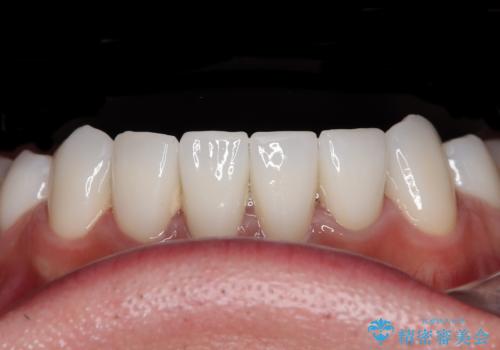

薬剤の影響で変色した歯を自然に オールセラミッククラウンによる審美歯科治療

- 口元の突出感を改善するための抜歯矯正を終えた患者様ですが、幼少期からの変色した歯をセラミッククラウンにて自然な色合いに変えていくこととしました。

口を開けたときに目につく範囲を希望されたため上下ともに8本ずつをオールセラミッククラウンによる補綴治療を行うこととしました。

近年では大変珍しいですが、胎児あるいは乳幼児期の抗生物質の影響で永久歯が変色してしまうことがあります。

ホワイトニングでの改善は期待できないため、オールセラミッククラウンによる補綴治療が必要となります。